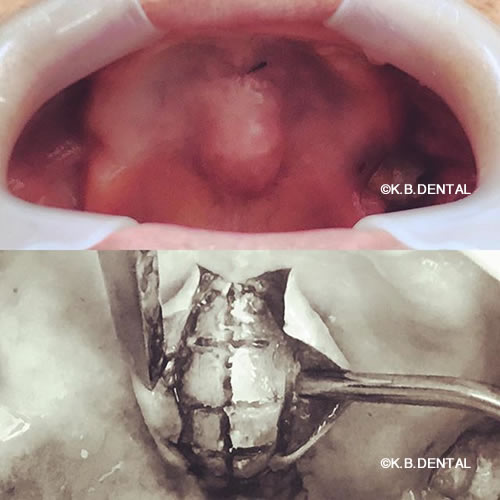

口蓋隆起(こうがいりゅうき)

口蓋隆起 症例1

噛む力の強い方に起きやすいケースです。上顎の総入れ歯が入れられないということで来院されました。なぜこのように上顎の骨が出てくるかというと、例えば、家の屋根があったとして、上から力がかかると応力で屋根の真ん中がたわんできます。

それと同じように正中口蓋の真ん中に亀裂(ヒビ)が入らないように、人間の体も生体防御反応で守ろうとし、真ん中に骨を作ろうとして骨添加が起きます。トレーニングでベンチプレスをする方でも、最初は腕が細い人がプルプル震えると思います。繰り返すうちに、だんだんと腕の骨の周囲を筋肉が肥大して腕を支えてくれます。それと同じような現象です。

料金

静脈内鎮静法による麻酔代込み:約15万円(保険適用外)